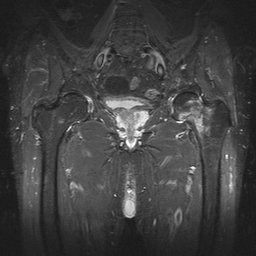

- Click on the image for a larger versionBAP radiograph of the left hip. There is a subtle band of sclerosis at the femoral neck.

- Click on the image for a larger versionCCoronal MRI. This STIR sequence image shows intense signal in the left femoral neck region, due to fracture much more extensive than that predicted by the radiograph. This was a Garden II fracture.